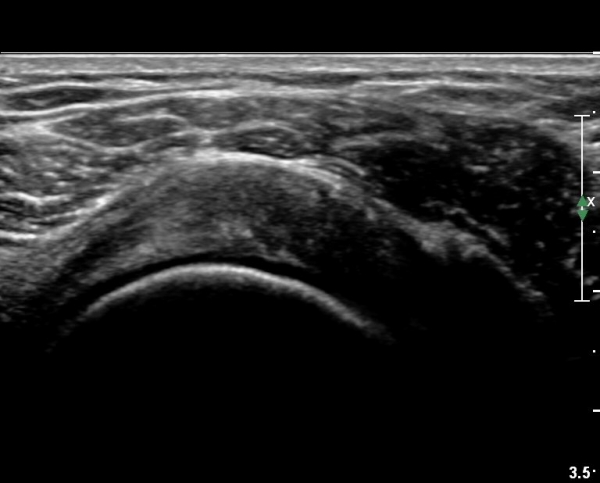

ÃÊÀ½ÆÄ °Ë»ç

´ë°áÀý°ú °ßºÀÇϺο¡ ¹æ»ç¼± Åõ°ú¼º °¨¼Ò(sclerosis)°¡ °üÂûµÈ´Ù(÷ºÎÆÄÀÏ).